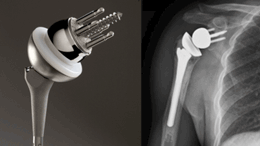

역행성인공관절치환술